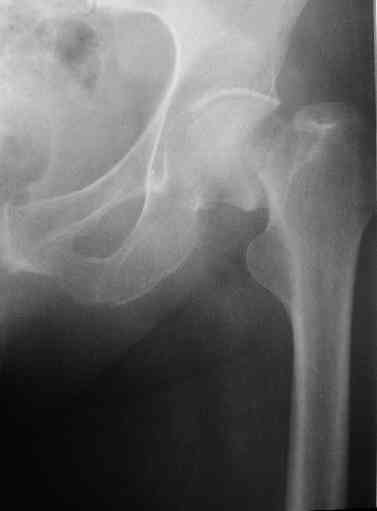

Представленные снимки неудачны ни по качеству, ни по обзорности. Классификационно предположительно Ванкувер В2. Накостный остеосинтез LCP с использованием монокортикальной фиксации в проксимальном отделе.

Представленные снимки неудачны ни по качеству, ни по обзорности.

? На фасных проекциях видно все до коленного сустава - куда ж больше обзорность? Качество IMHO совершенно обычное, приемлемое, весь перелом виден...

Классификационно предположительно Ванкувер В2.

B2 - это перелом около конца ножки с ее нестабильностью. Здесь же перелом б.вертела вдоль всей ножки.

1. Представляющей наибольшую ценность из представленной информации следует считать фасные снимки №3и №4 (если считать по порядку). На снимке №3 не видны ни проксимальный отдел бедра с зоной (линией) перелома - наложение тени, ни дистальная зона (линия) перелома - область не захвачена. Снимок №4 демонстрирует дистальную линию перелома, но не показывает уровень конца ножки эндопротеза. В таких сучаях как способ можно выполнять снимок "с метками" - чтобы при при наложении снимков на негатоскопе иметь целостностное представление о всём сегменте от тазобедренного до коленного суставов.

2. Не совсем так. Перелом В2 (по C. Duncan и B.A.Masri, 1995) - перелом на уровне ножки эндопротеза или непосредственно дистальнее её конца с нестабильностью ножки, но хорошим качеством кости проксимального отдела бедра. Как известно, по статистике - наиболее часто встречающийся тип перипротезного перелома при первичном эндопротезировании. Очевидно - продольное раскалывание проксимального фрагмента в данном случае вызовёт нестабильность ножки.